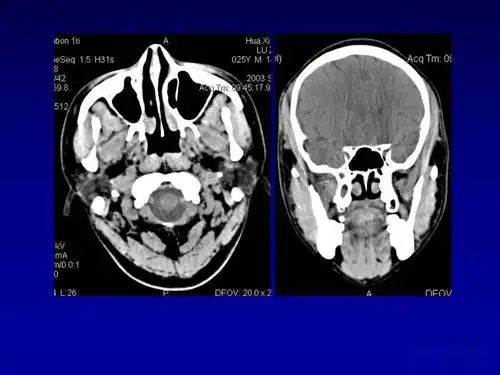

颌面部解剖及其病变的影像诊断_处理